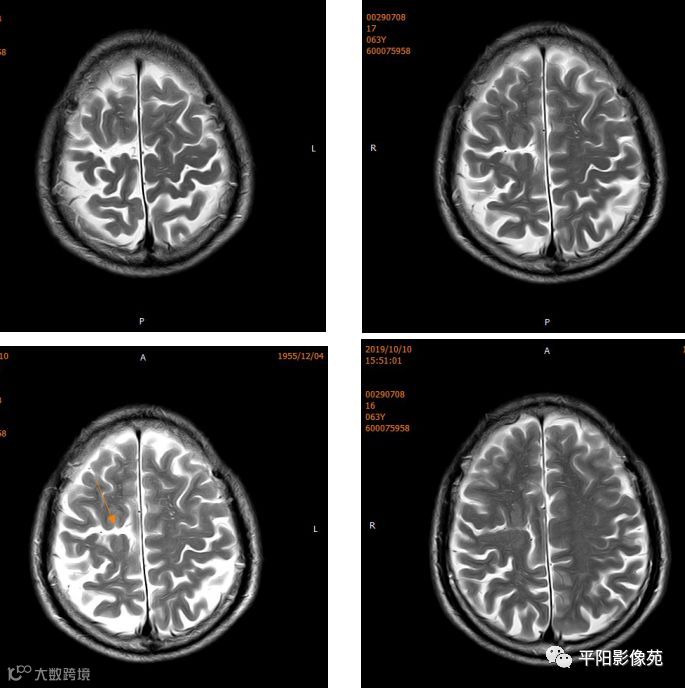

右侧额叶中央前回局部脑裂增宽,并向内延伸,周围衬以等灰质信号,呈稍长T1稍长T2信号,病灶自软脑膜向内延伸,与室管膜相连。